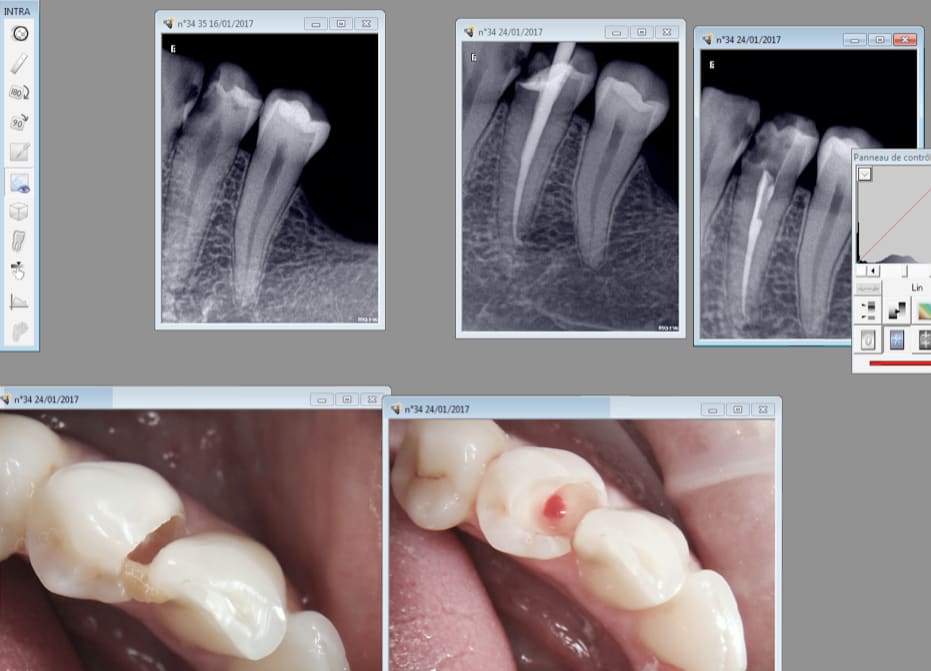

Bonjour à tous, je tiens avant tout à vous remercier pour vos suggestions et voici une radio.

ps: je tiens à préciser que la 42 présentait déjà une obturation canalaire incomplète (comme vous pouvez remarquer).

Tiens encore un exemple.

40 mn de A à Z endo taille empreinte provisoire. Et encore tu perds du temps en unitaire. Quand tu les fais en rang d'oignons tu gagnes du temps. Ca permet de réduire les couts. Ca devrait intéresser Mr Revel non ? -)